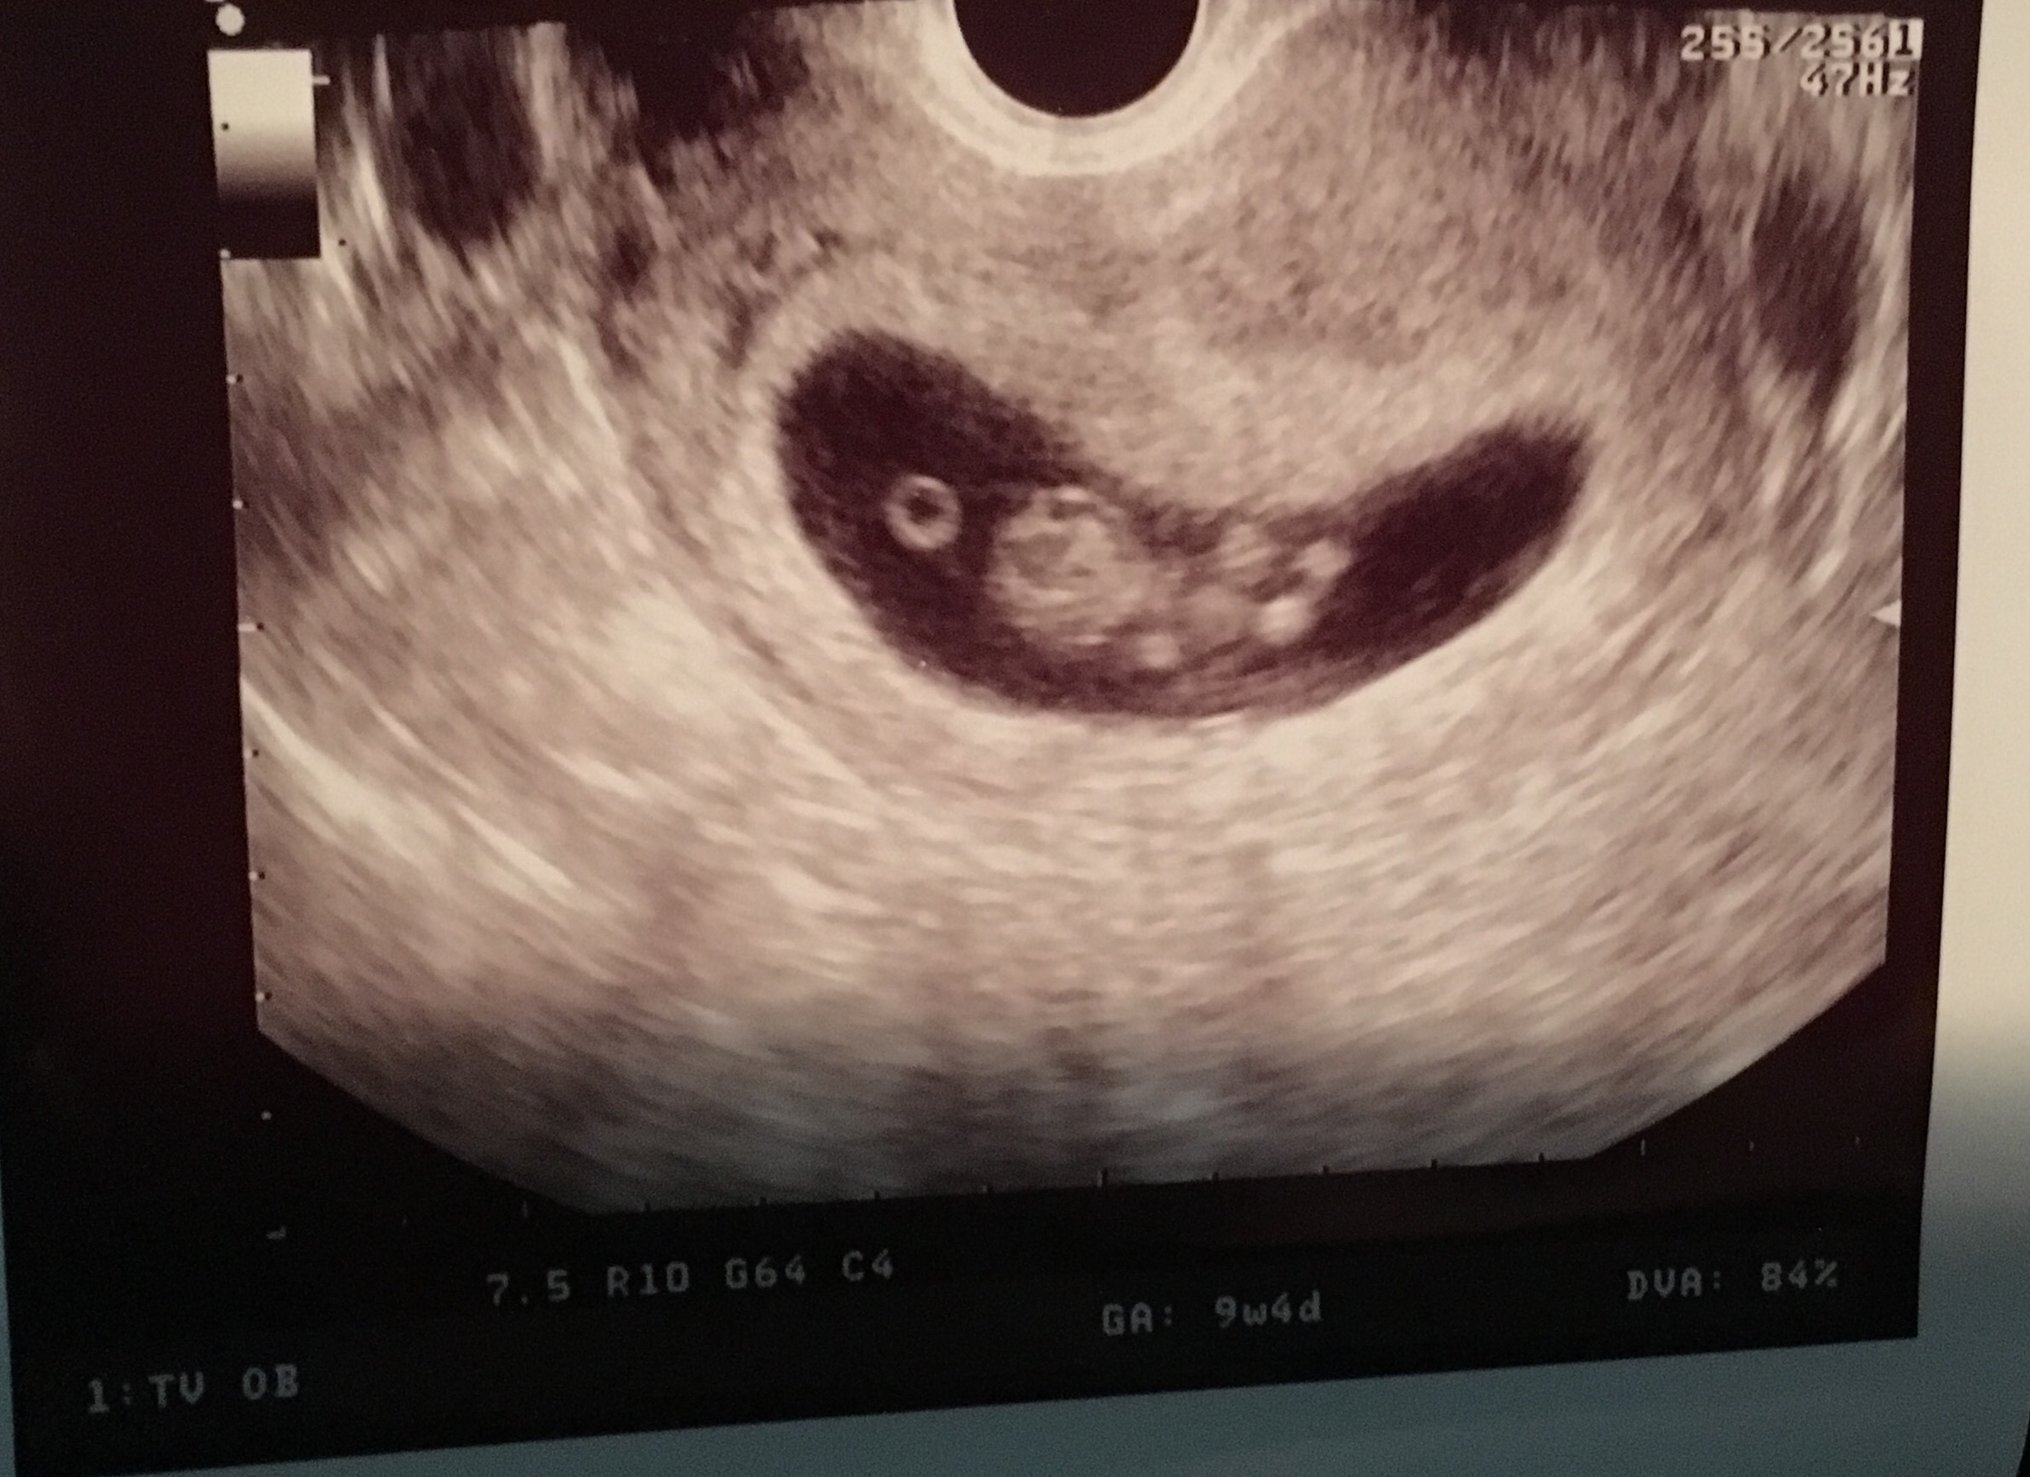

Little one came in right on time at 9 weeks 4 days strong hr at 176. Looks like we are in the clear and pgal brain can go away. Next appt on the 16th to get Harmony test done.